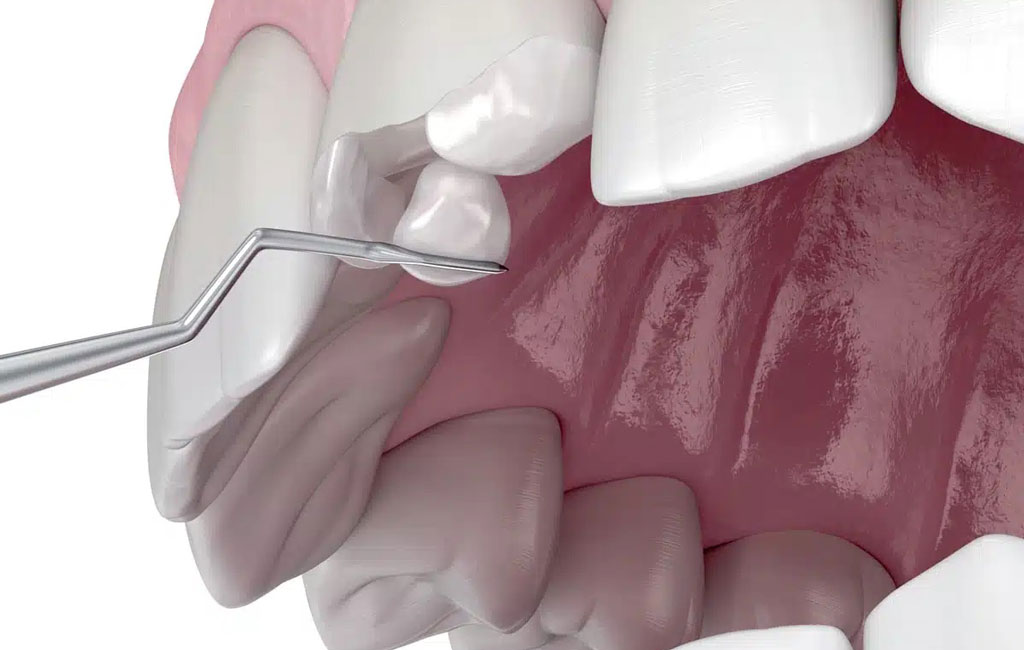

- آماده سازی دندان: دندانپزشک دندان را تمیز میکند و در صورت وجود پوسیدگی، آن را برطرف میکند.

- قرار دادن مواد همرنگ: ماده به صورت لایهلایه روی دندان قرار میگیرد و هر لایه با نور مخصوص سفت میشود تا استحکام کافی داشته باشد.